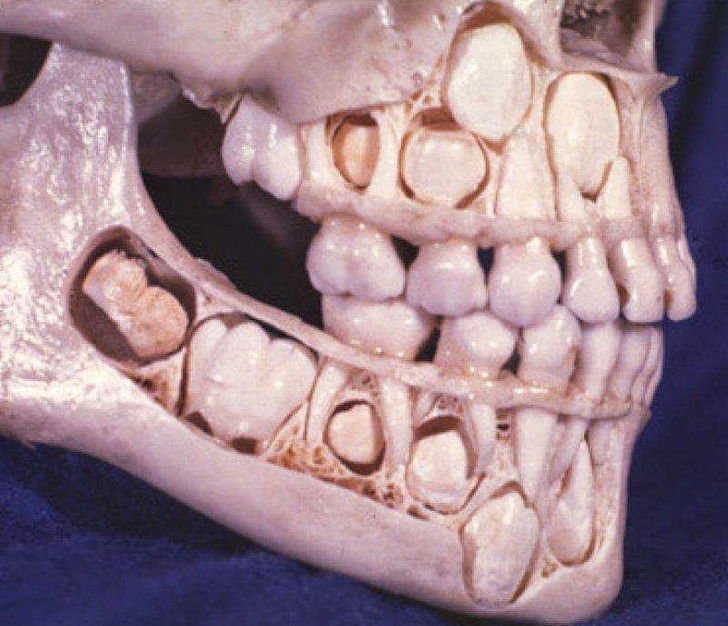

10. Đây là hình ảnh về những chiếc răng trước khi mọc.

![]() |